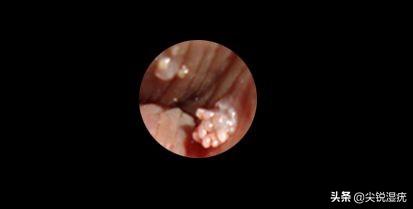

诊断尖锐湿疣最重要的依据就是看局部症状,一旦长出了赘生物,且逐渐增生增多,形成了典型的菜花样、鸡冠样或乳头样形状。这样的情况多考虑是尖锐湿疣。